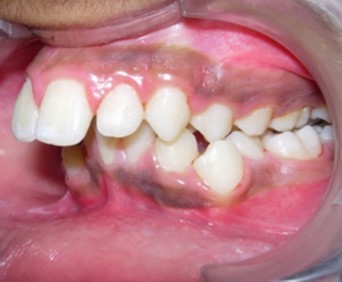

Intraoral assessment. (Figure 1d,Figure 1e,Figure 1f,Figure 1g,Figure 1h).

Figure 1f.Pre-treatment intra-oral-Left

Pre-treatment intra-oral-Left

The maxillary arch was V-shaped with severely proclined and rotated maxillary incisors with a palatally placed 12. The mandibular arch was U-shaped with severe crowding of mandibular incisors, with 43 partially erupted and buccally placed with transpositioned 42 and 43, with 42 mesiolingually rotated, 33 distolingually rotated and 34 distolingually rotated and buccally placed.

Severe increase in overjet and deep bite were both observed. The maxillary midline coincided with the skeletal midline but the mandibular midline was shifted to the right side by 1 mm. Bilateral maxillary posterior crossbite was also observed. On right side the molar relation was Class I and on the left side it was Class II. The canine relation was Class II on the left side and the curve of Spee was increased.